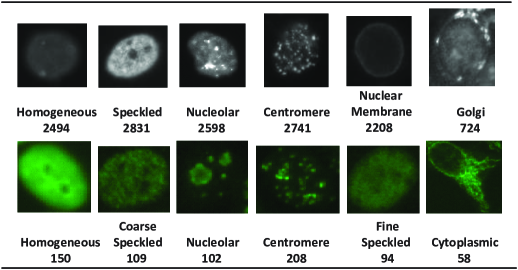

ICPR2014 cell dataset. This dataset contains training cell images, and the test set is reserved by the competition organizers and not published yet. The cell images are extracted from specimen images captured by monochrome high dynamic range cooled microscopy camera fitted on a microscope with a plane-Apochromat / objective lens and an LED illumination source (Lovell et al., 2014). These specimen images have been automatically segmented by using the DAPI channel and manually annotated by specialists. Each image belongs to one of the six staining patterns: Homogeneous, Speckled, Nucleolar, Centromere, Nuclear Membrane and Golgi, as shown in the top row of Fig. 3.

ICPR2012 cell dataset. It consists of cell images extracted from specimens, which are acquired with a fluorescence microscope (-fold magnification) coupled with W mercury vapor lamp and with a digital camera (Foggia and Vento, 2013). The dataset is pre-partitioned into training set ( images) and test set ( images). Each image belongs to one of the six classes: Homogeneous, Coarse Speckled, Nucleolar, Centromere, Fine Speckled and Cytoplasmic, as shown in the bottom row of Fig. 3.

Comparing the two datasets shows that two of the six classes are different. Specifically, two sub-categories of ICPR2012 dataset (Fine Speckled and Coarse Speckled) are merged into one category (Speckled) in ICPR2014 dataset, and two less frequent staining patterns appearing in daily clinical cases, Golgi and Nuclear Membrane are introduced in ICPR2014 dataset for developing more realistic HEp- cell classification systems. Moreover, because the images in the two datasets are captured with different laboratory settings, a classification system that can be easily transferred from one dataset to the other one will be highly desired.